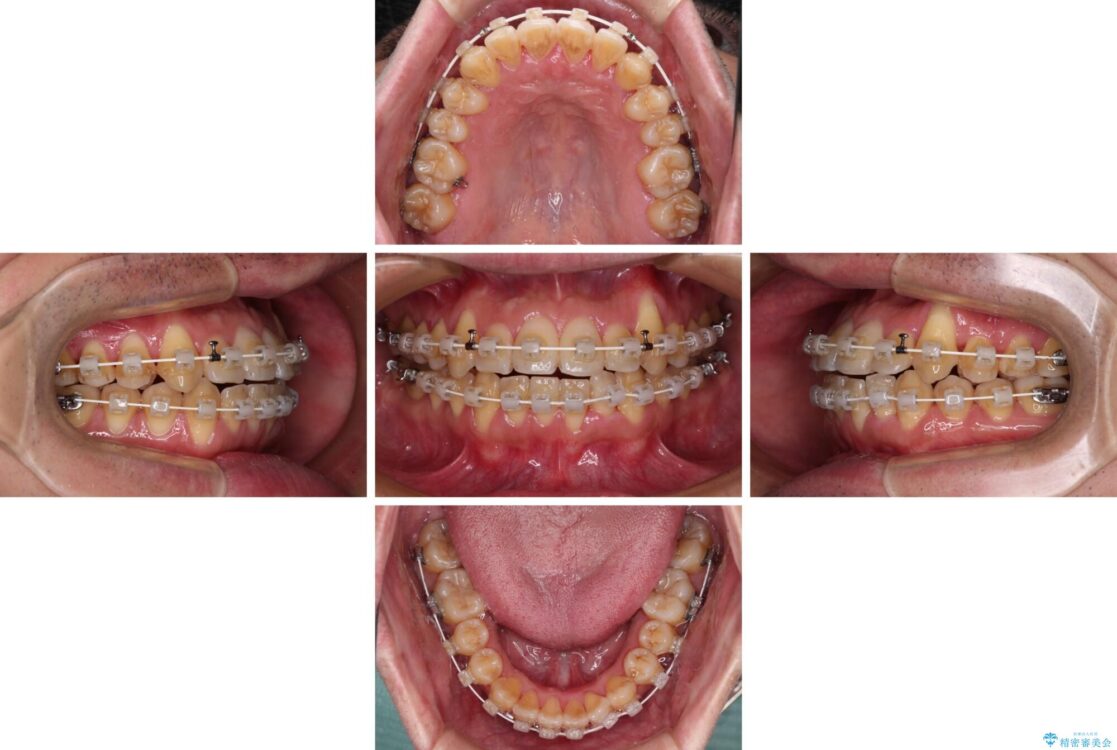

治療途中

• 八重歯とクロスバイト 目立たないワイヤー装置で矯正治療 治療途中画像